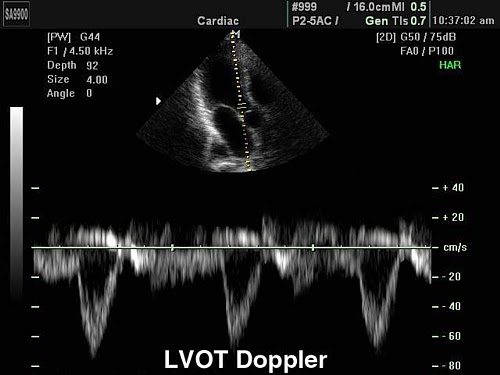

PW импульсно-волновой допплер

Применяют в эхокардиографии для количественной оценки кровотока в сосудах с высокоскоростными потоками.

Также с помощью импульсного допплера можно зафиксировать щелчки открытия и закрытия створок клапанов, дополнительные сигналы от хорд створок и стенок сердца.